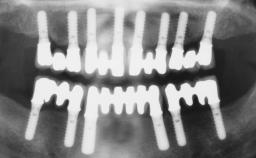

Immediate Loading of Six Implants in the Maxilla and Final Restoration with a Full-Arch CAD/CAM Zirconia FDP

# of Implants 6

Bone Augmentation Horizontal|Simultaneous

Defining Characteristics Fully edentulous upper jaw to be rehabilitated with four or more implants

Modality 6+ implants with immediate loading

Bone Volume Horizontally and vertically sufficient